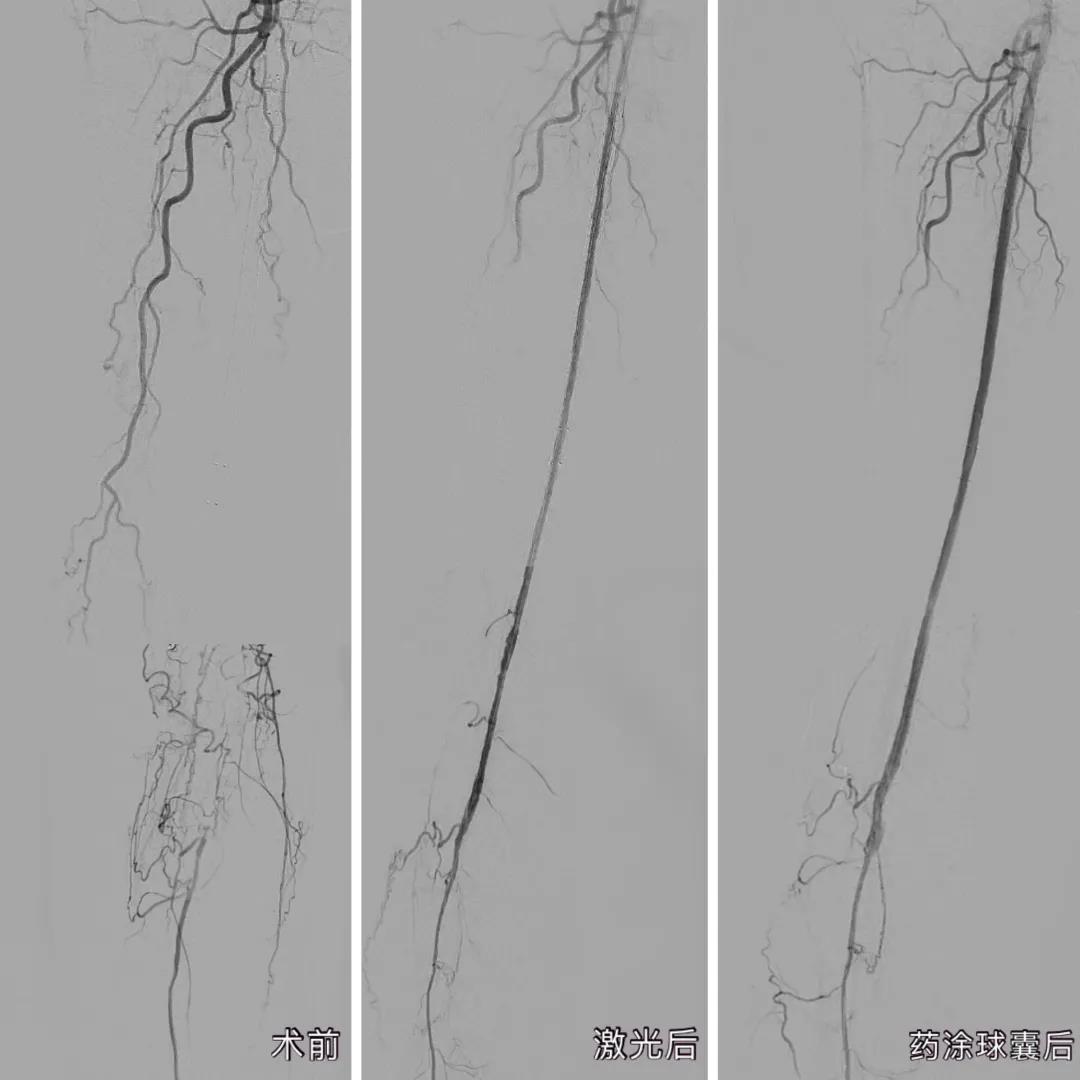

患者手术前后下肢动脉血管造影对比

手术过程顺利,术后造影结果下肢动脉病变部位全程血流通畅。经过厦心护理团队的细心看护,郑奶奶手术后第二天就可以下床活动,术后不到一周便解除了疼痛,完全正常行走。

经过完善的术前准备,庄晖主任率团队在患者大腿的动脉,穿刺了一个仅绿豆般大小的口子,将激光导管从小洞中引入到堵塞的血管中,用准分子激光进行开通。仅是激光消蚀减容还不够,医生又使用了药物涂层球囊,通过球囊扩张,将一种防止内膜增生的药物涂到血管内壁上,从而达到长期抑制血管再狭窄的效果,“通俗来说,就是起到防止血管内再长‘水垢’的作用。”